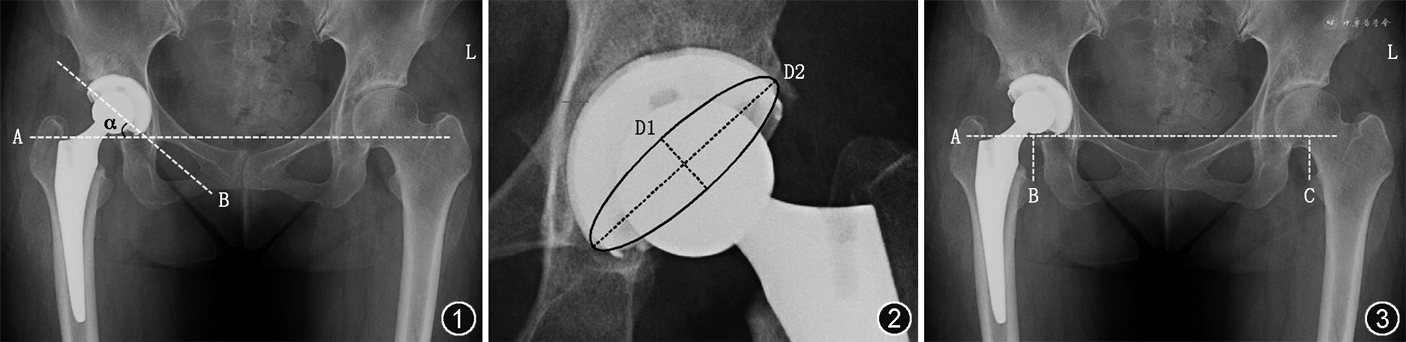

髋臼假体的外展角和前倾角均在骨盆前后位X线片上进行测量。髋臼假体的外展角定义为髋臼杯口的连线与两侧髋臼泪滴连线的外侧夹角(图1)。髋臼假体的前倾角通过Lewinnek等[8]提出的测量方法进行测量,公式为:假体前倾角=arcsin(D1/D2)。

其中D1为髋臼杯口椭圆形的短轴,D2为髋臼假体的长轴,亦即髋臼假体的最大直径(图2)。这种方法通过三角函数的计算可以测量出髋臼杯的倾斜角度,但是无法辨别倾斜的方向,因此所有患者还要通过髋关节穿桌侧位X线的检查,使用Woo和Morrey[9]的方法来辨别髋臼杯是前倾还是后倾。

术前和术后下肢长度的差异在骨盆前后位X线片上进行测量。计算双侧股骨小粗隆尖至两侧髋臼泪滴连线的垂直距离,术侧与对侧距离的差值,即定义为下肢长度的差异(图3)。正值为术侧延长,负值为术侧缩短,精确至毫米。